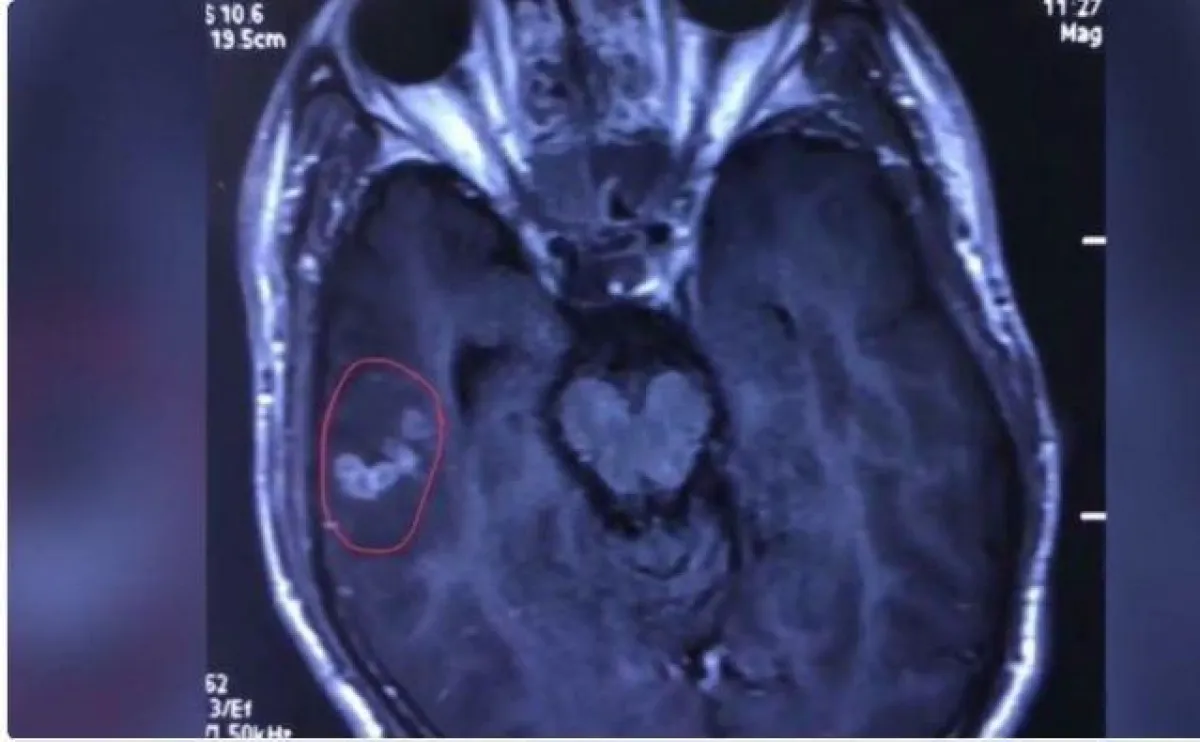

كما حدّد أطباء الجراحة، مكان الدودة في دماغ المريض، وبعدها أُجريت له عملية استخرجت فيها الدودة الشريطية من دماغه.